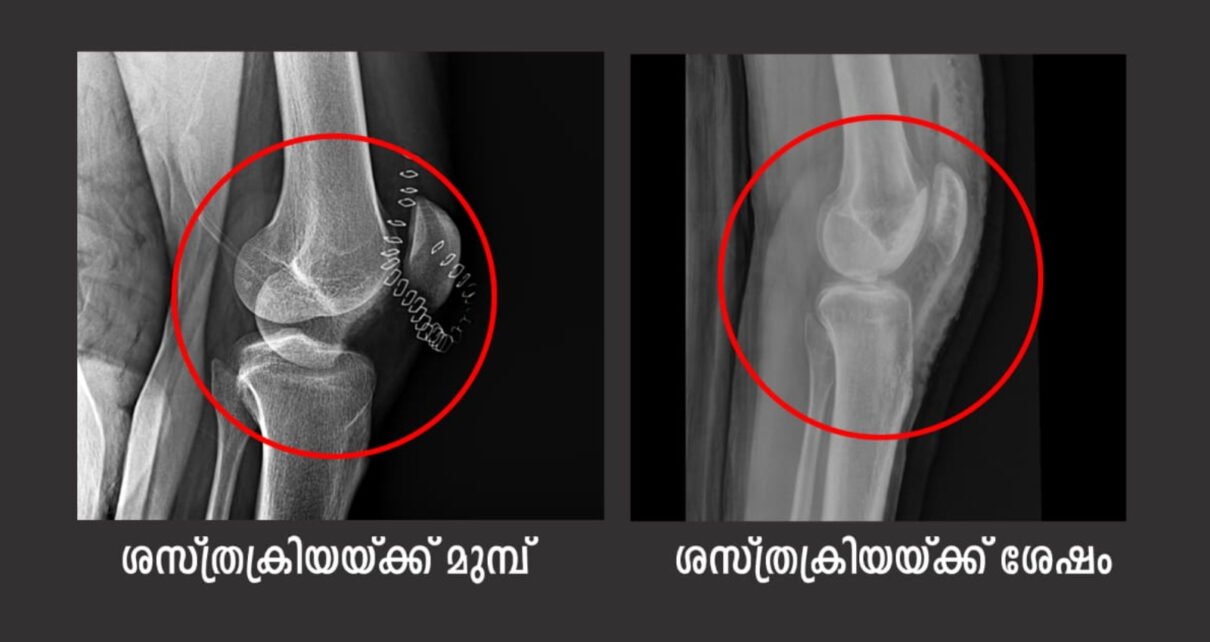

കായംകുളം സ്വദേശിയായ യുവാവിനാണ് ഏഴ് മാസം മുൻപ് നടന്ന വാഹനാപകടത്തിൽ കാൽമുട്ടിനുള്ളിലെ കാർട്ടിലേജും, അസ്ഥിയും നഷ്ടപ്പെട്ടത്. മുട്ടിലുണ്ടായ ഗുരുതര മുറിവിലൂടെ അഞ്ച് സെന്റിമീറ്റർ വലുപ്പത്തിൽ കാർട്ടിലേജും അസ്ഥിയും അടർന്ന് റോഡിൽ നഷ്ടപ്പെടുകയായിരുന്നു.

ചെങ്ങന്നൂരിലെ സ്വകാര്യ ആശുപത്രിയിൽ കാൽമുട്ടിലെ പ്രാഥമിക ശസ്ത്രക്രിയക്ക് ശേഷം ഇടുപ്പിലെ ഗുരുതരമായ അസിറ്റാബുലർ ഫ്രാക്ചറിന്റെ ചികിത്സക്കായി മാർ സ്ലീവാ മെഡിസിറ്റിയിലേക്ക് മാറ്റുകയായിരുന്നു. തുടർന്ന് നടത്തിയ വിദഗ്ധ പരിശോധനയിലാണ് തുടയെല്ലിന്റെ താഴെയായി മുട്ടിനുള്ളിൽ ഭാരം താങ്ങുന്ന ഭാഗത്ത് അസ്ഥിയും തരുണാസ്ഥിയും നഷ്ടപ്പെട്ടതായി കണ്ടെത്തിയത്.

മുട്ടിലെ അസ്ഥിയിലെ വലിയ വിടവ് മൂലം യുവാവിന് ഭാരം താങ്ങി നടക്കാൻ സാധിക്കില്ലാത്തതിനാൽ ഒന്നുകിൽ കൃത്രിമ സന്ധി ഘടിപ്പിക്കുകയോ അല്ലെങ്കിൽ അവയവമാറ്റത്തിലൂടെ അസ്ഥിയും തരുണാസ്ഥിയും മാറ്റി സ്ഥാപിക്കുകയും ചെയ്യുക എന്നത് മാത്രമായിരുന്നു മാർഗങ്ങൾ.

മൂന്ന് മണിക്കൂർ നീണ്ട ശസ്ത്രക്രിയയിലൂടെ കാർട്ടിലേജ് – ബോൺ കോംപ്ലക്സ് മാറ്റി സ്ഥാപിച്ചു.. ശസ്ത്രക്രിയയ്ക്ക് ശേഷം വേദന കുറഞ്ഞ യുവാവ് മുട്ട് മടക്കാൻ തുടങ്ങുകയും ഏതാനും ദിവസത്തിനുള്ളിൽ ആശുപത്രിയിൽ നിന്നു സുഖം പ്രാപിച്ചു മടങ്ങുകയും ചെയ്തു.